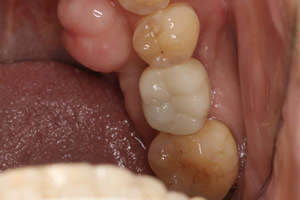

症例1

- 年齢・性別

- 55歳女性

- 治療期間

- 2ヶ月

- 抜歯

- なし

- 治療費

- 66万円

- 備考

- 右下6.7欠損

- 治療内容

- 右下6.7欠損部にインプラント埋入

- 施術の副作用(リスク)

- オペによる知覚障害。インプラントによる歯肉炎。インプラント脱落。